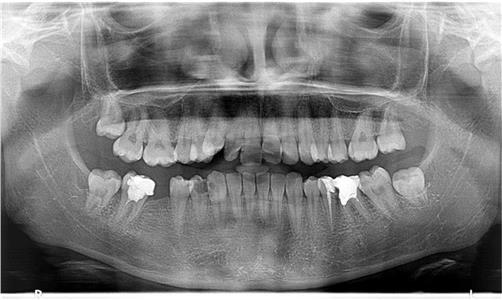

Современата ендодонција е целосно застапена во нашата ординација. Тоа вклучува примена на апекс локатор (за прецизно одредување на должината на коренските канали), системи за машинска обработка на истите (Protaper, Endo eze), системи за иригација (испирање) и дезинфекција на каналите, ласер за комплетна стерилизација, високо квалитено полнење и секако потврда на спроведениот ендодонтски третман со рентген снимка.

ЕНДОДОНЦИЈА